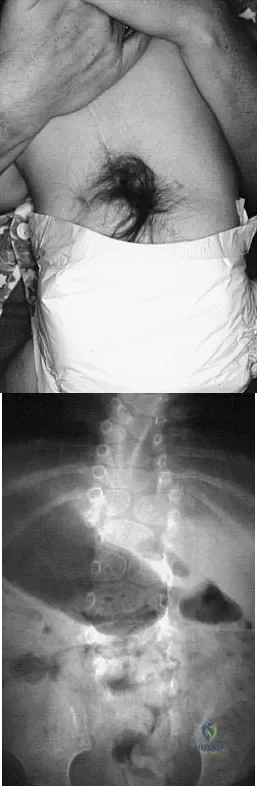

Question 73

A 4-month-old infant is referred for evaluation of congenital scoliosis. The child has no congenital heart anomalies, and a renal ultrasound shows that he has one kidney. Examination reveals mild scoliosis and a large hairy patch on the child's back. Neurologic evaluation is normal for his age. A clinical photograph and radiograph are shown in Figures 19a and 19b. Initial management should consist of

Explanation